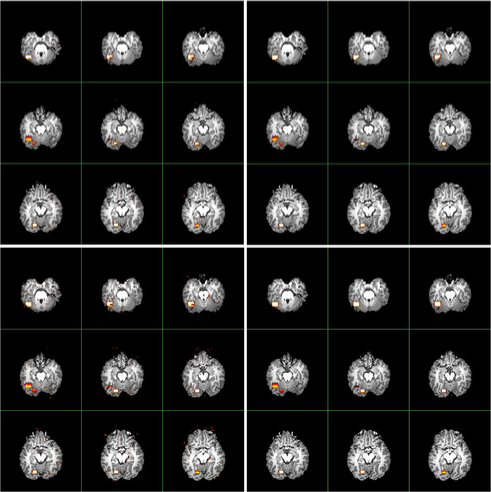

Figure 7 compares the activated brain regions identified by the (in the left panels) and (in the right panels) procedures. Owing to the wealth of data, and for purposes of computational simplicity, results using Method I of are presented. Voxel-wise inactivity is tested with the semi-parametric test statistics (in the top panels) and (in the bottom panels) whose notation was given and asymptotic distributions were derived in Zhang and Yu (2008). The control level is . Inspection of FigureΒ 7 reveals that and locate both active regions. In particular, using the procedure, both methods detect more than voxels (which are visible when zooming the images), many of which are falsely discovered. When applying the procedure, detects voxels, whereas detects voxels. Thus the procedure reduces the number of tiny scattered false findings, gaining more accurate detections than the procedure.

As a comparison, the detection results by popular software AFNI [Cox (1996)] and FSL [Smith et al. (2004) and Woolrich et al. (2001)] are given in Figure 8. We observe that both AFNI and FSL fail to locate one activated brain area, and that the other region, though correctly detected, has appreciably reduced size relative to the actual size. This detection bias is due to the stringent assumptions underlying AFNI and FSL in modeling fMRI data: the Hemodynamic Response Function (HRF) in FSL is specified as the difference of two gamma functions, and the drift term in AFNI is specified as a quadratic polynomial. As anticipated, applying the distributions restricted to parametric models to specify the distributions of test statistics in AFNI and FSL leads to bias, which in turn gives biased calculations of -values and -values. In this case, the detection performances of both the and procedures deteriorate, and the procedure does not improve the performance of the procedure. See Table 3 for a more detailed comparison.

A comparison of the activated brain regions using the and procedures is visualized in Figure 9. The level is used to carry out the multiple comparisons. The conventional procedure finds more tiny scattered active voxels, which are more likely to be falsely discovered. In contrast, the procedure finds activation in much more clustered regions of the brain.